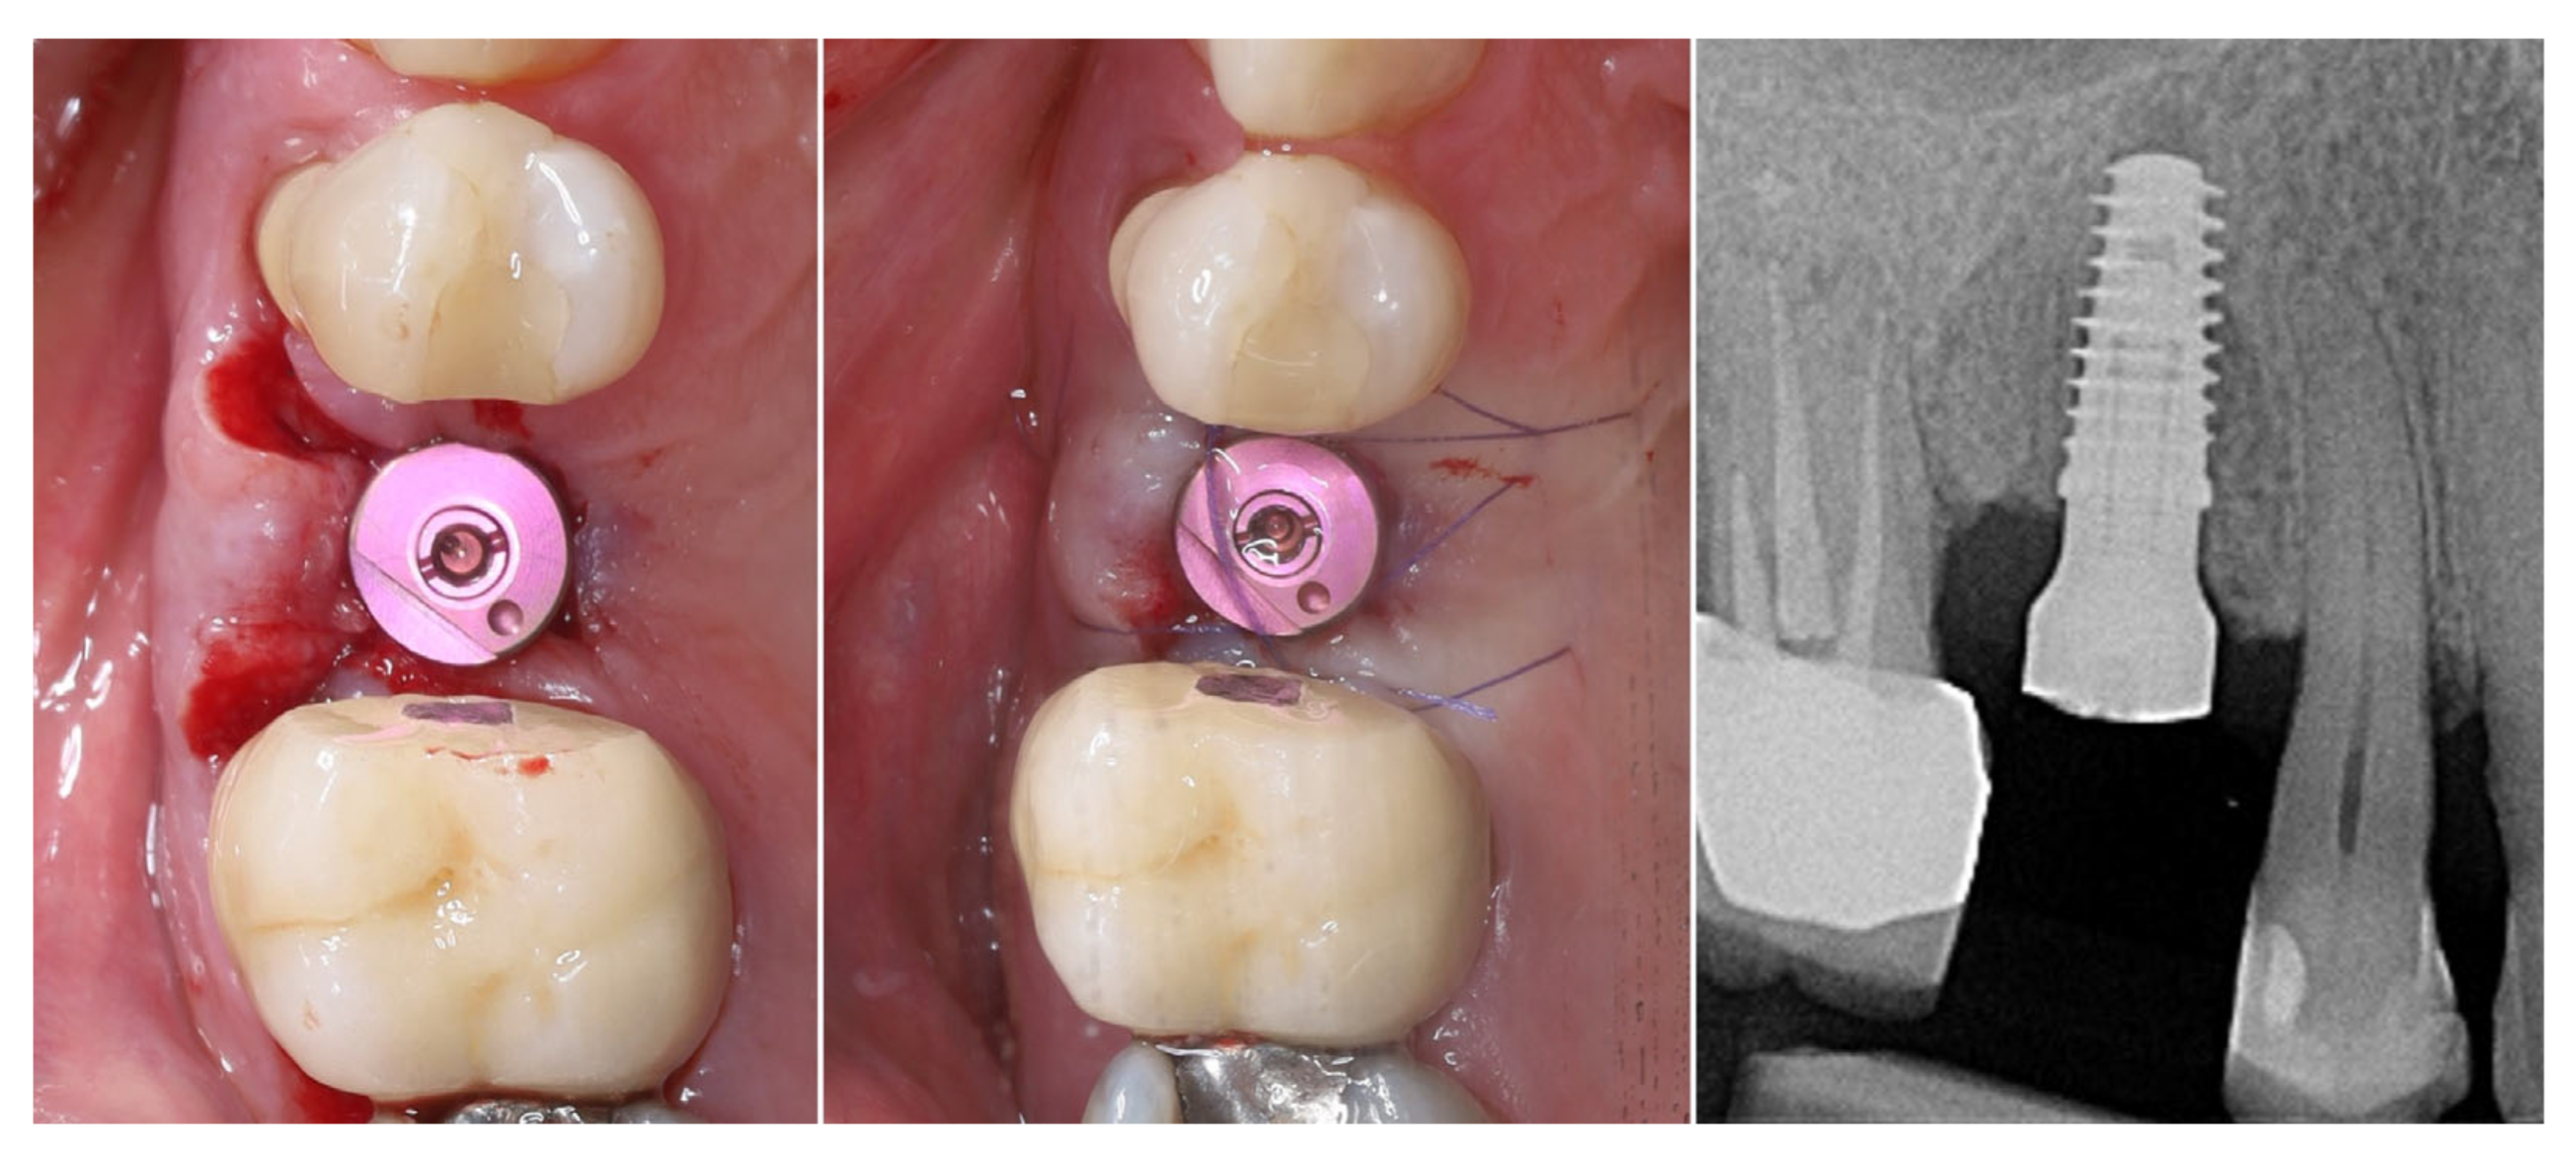

The implant was placed using a digitally designed surgical guide to ensure prosthetically driven positioning. Intraoperative images demonstrate the sequence of guided placement: preparation of the osteotomy through the guide with visualization of the prepared site (left), dental implant (T3Pro, ZimVie Inc., Palm Beach Gardens, FL, USA) before placement (middle), and final implant insertion (right) with insertion torque ~50N/cm. The use of a surgical template allowed precise three-dimensional implant placement, optimal angulation, and preservation of surrounding soft and hard tissues (Figure 8).

Figure 8.

Guided implantation protocol.

The selected implant was positioned in the prosthetically driven position, with appropriate bone thickness at the buccal aspect and surrounded by healthy soft tissues (left). Another advantage of this surgical approach is the possibility to adapt the implant insertion depth corresponding to the soft tissue thickness in order to provide enough soft tissue thickness to enhance the stability of the peri-implant bone. The intraoperative measurements confirmed excellent primary stability, with ISQ values of 82 bucco-lingually and 85 mesio-distally (right). These parameters indicated optimal mechanical anchorage of the fixture within the alveolar bone, ensuring favourable conditions for osseointegration (Figure 9).

Figure 9.

Implant placement and initial stability.